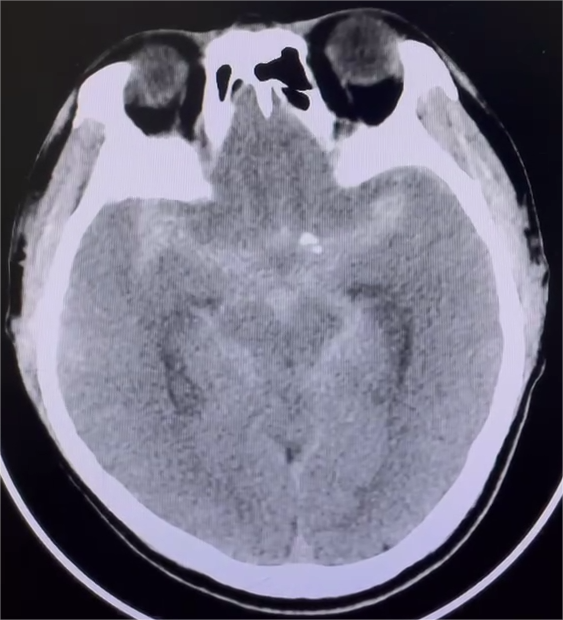

术前CT

术前CT